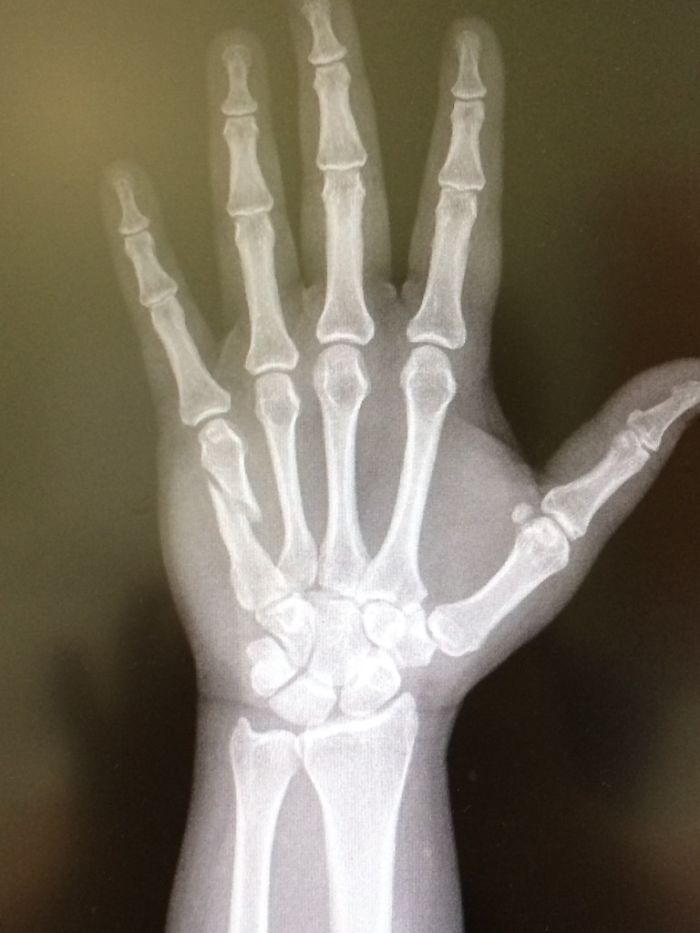

Polydactyl Claw X-Ray